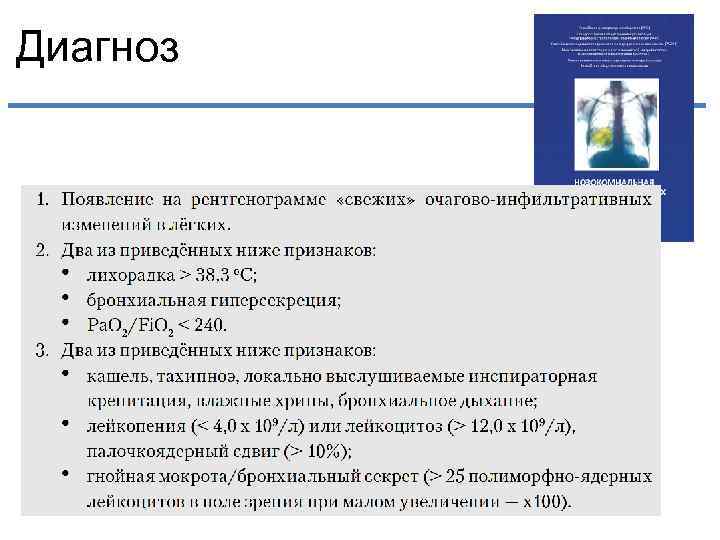

Диагноз

Диагноз

Диагноз ия г ло ио ы об сев кр по и М Рентген VAP Клиника: - Лихорадка -↓ оксигенации - Мокрота - Немые зоны - Лейкоцитоз • 3 компонента должны быть • При высокой степени тяжести

Диагноз ия г ло ио ы об сев кр по и М Рентген VAP Клиника: - Лихорадка -↓ оксигенации - Мокрота - Немые зоны - Лейкоцитоз • 3 компонента должны быть • При высокой степени тяжести